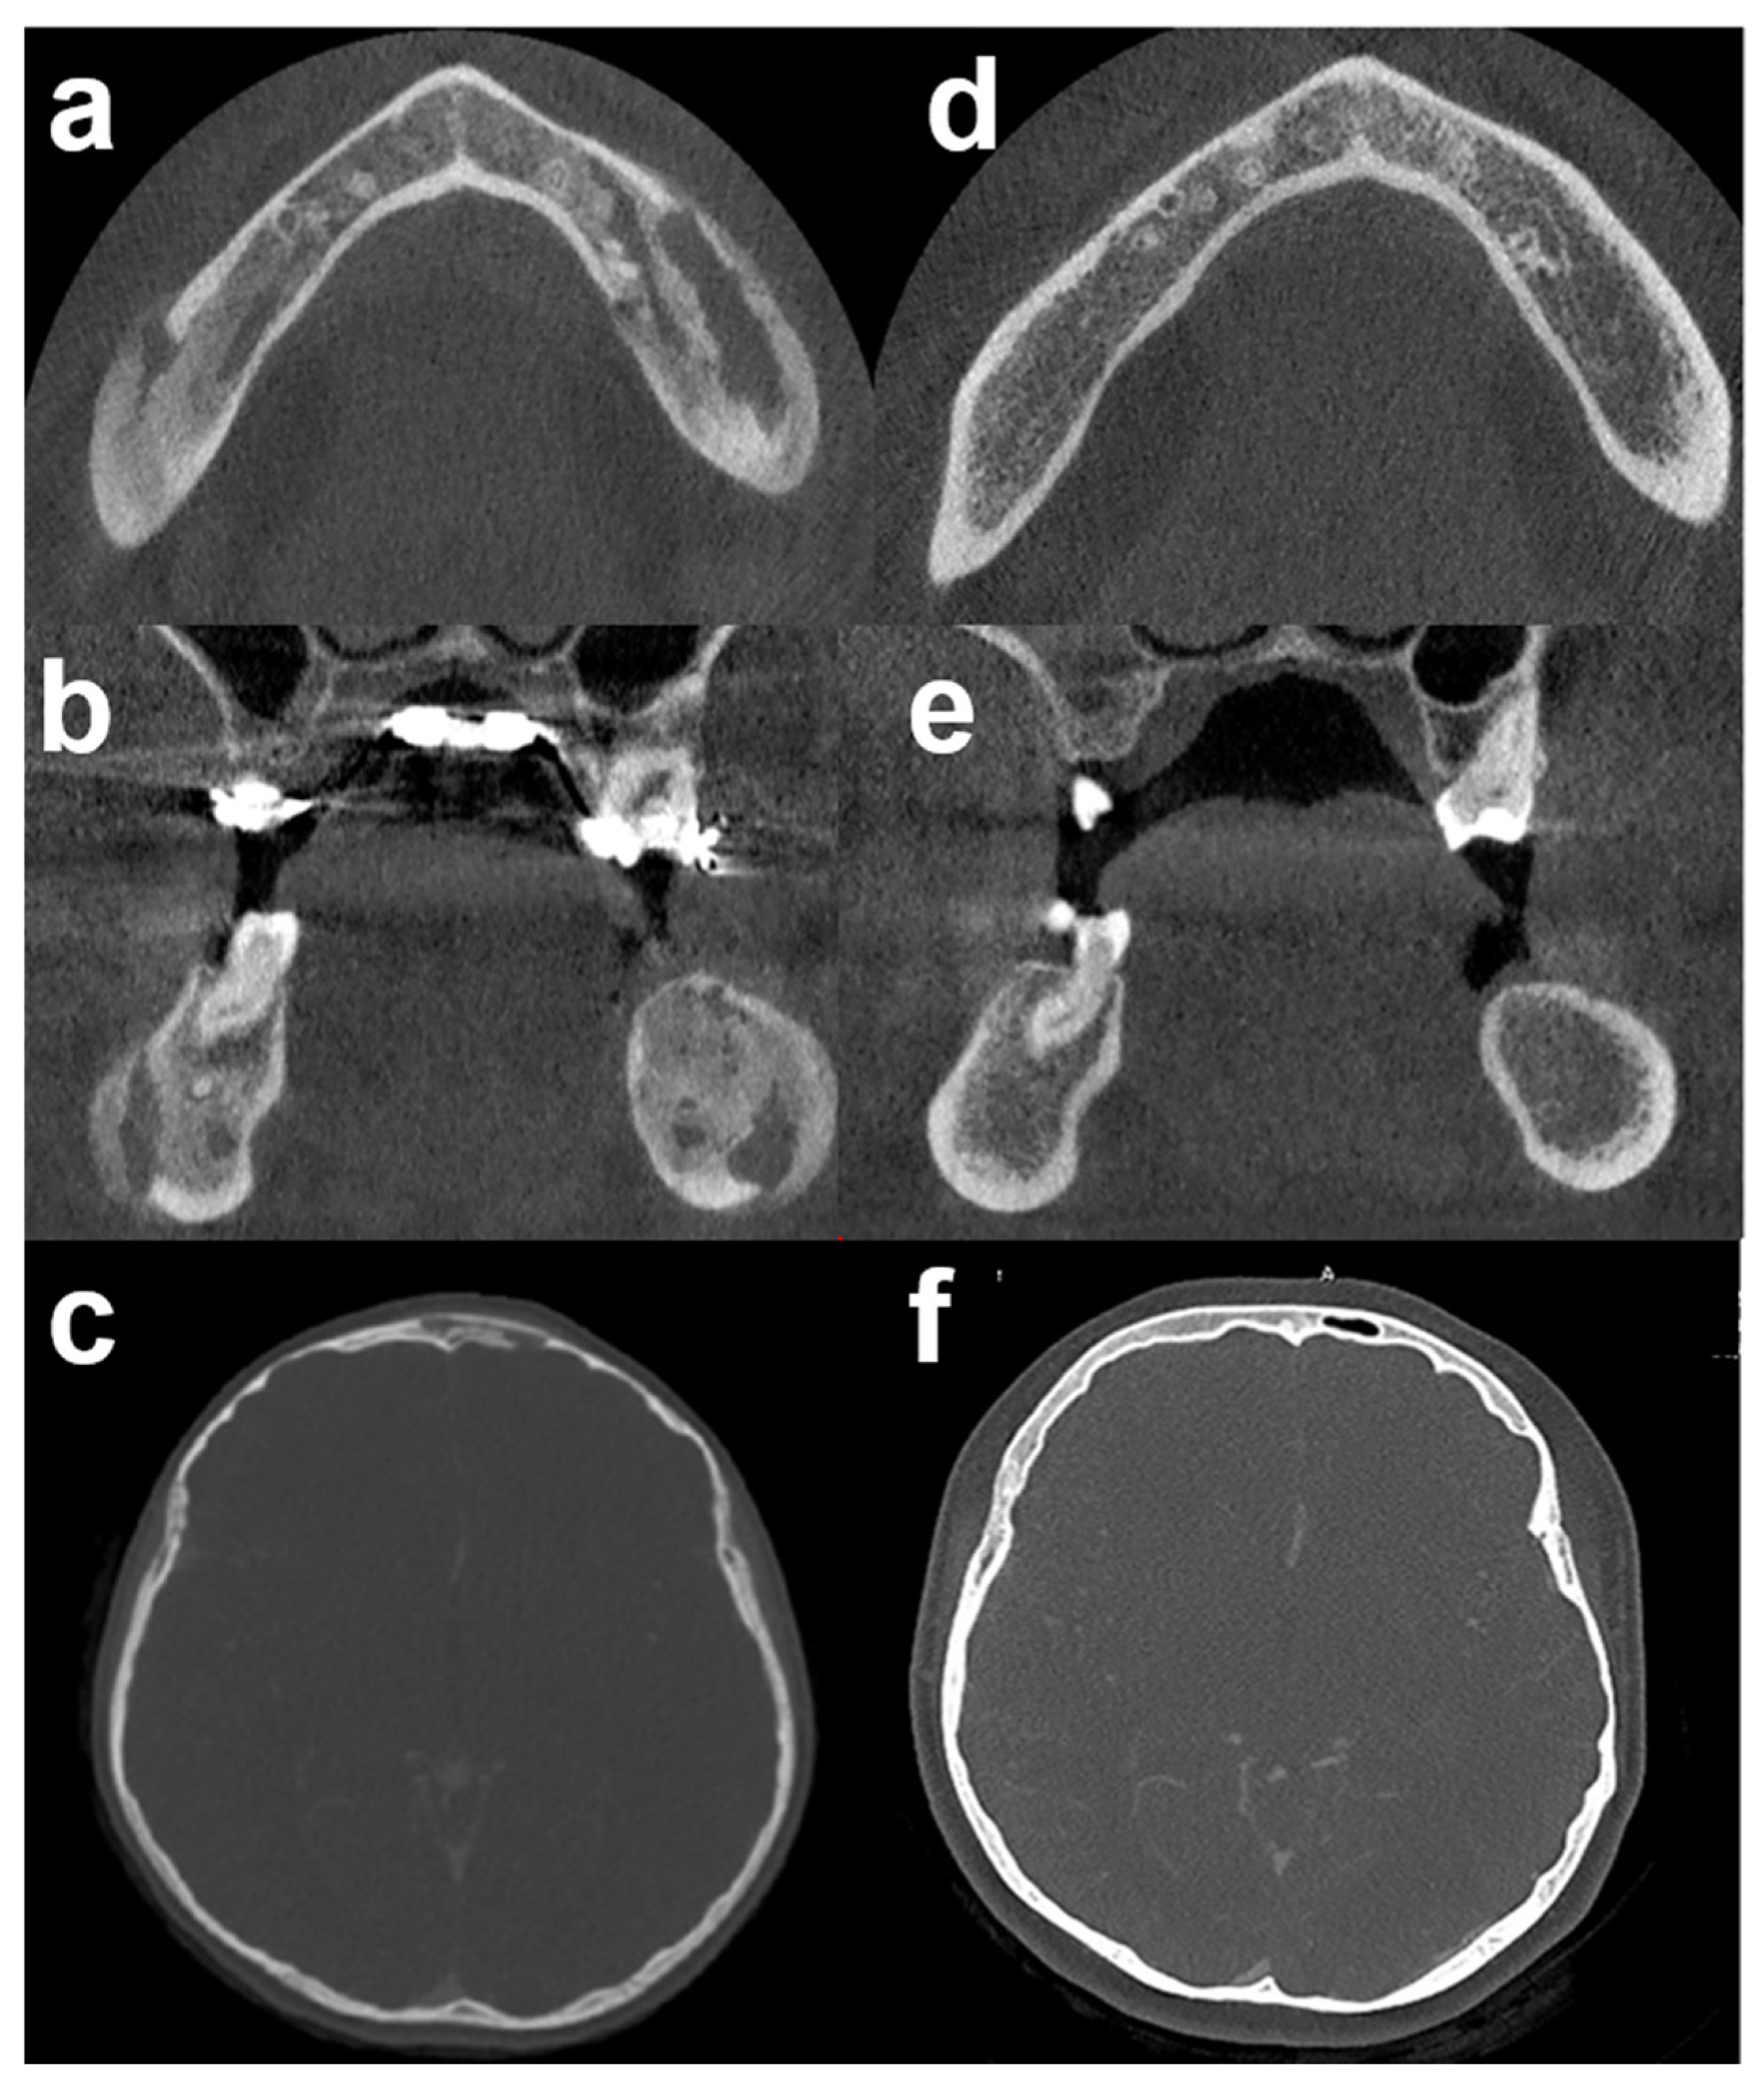

Based on these findings, a final diagnosis of chronic bacterial osteomyelitis was established. We initiated a 6-month course of oral antibiotic treatment with levofloxacin (500 mg, once a day) and cotrimoxazole (= trimethoprim/sulfamethoxazole, TMP/SMX) (400 mg/80 mg, two times a day). Periodic blood tests and renal function monitoring were performed with normal results. At 3 months, the patient was symptom-free. At 6 months, CBCT/CT scans showed a normal bone structure (Figure 4). At 2 years post-antibiotic treatment, no clinical or radiological relapse had been noted.

Figure 4. 3D computed tomography before and after antibiotic therapy: (ac) CBCT/CT scan before antibiotic therapy. (df) The corresponding CBCT/CT scan, 6 months after antibiotic therapy demonstrated complete bone healing. Bone sclerosis and osteolysis (mixt pattern) disappeared in mandible (d,e) and frontal bone (f). CBCT: Cone Beam Computed Tomography.